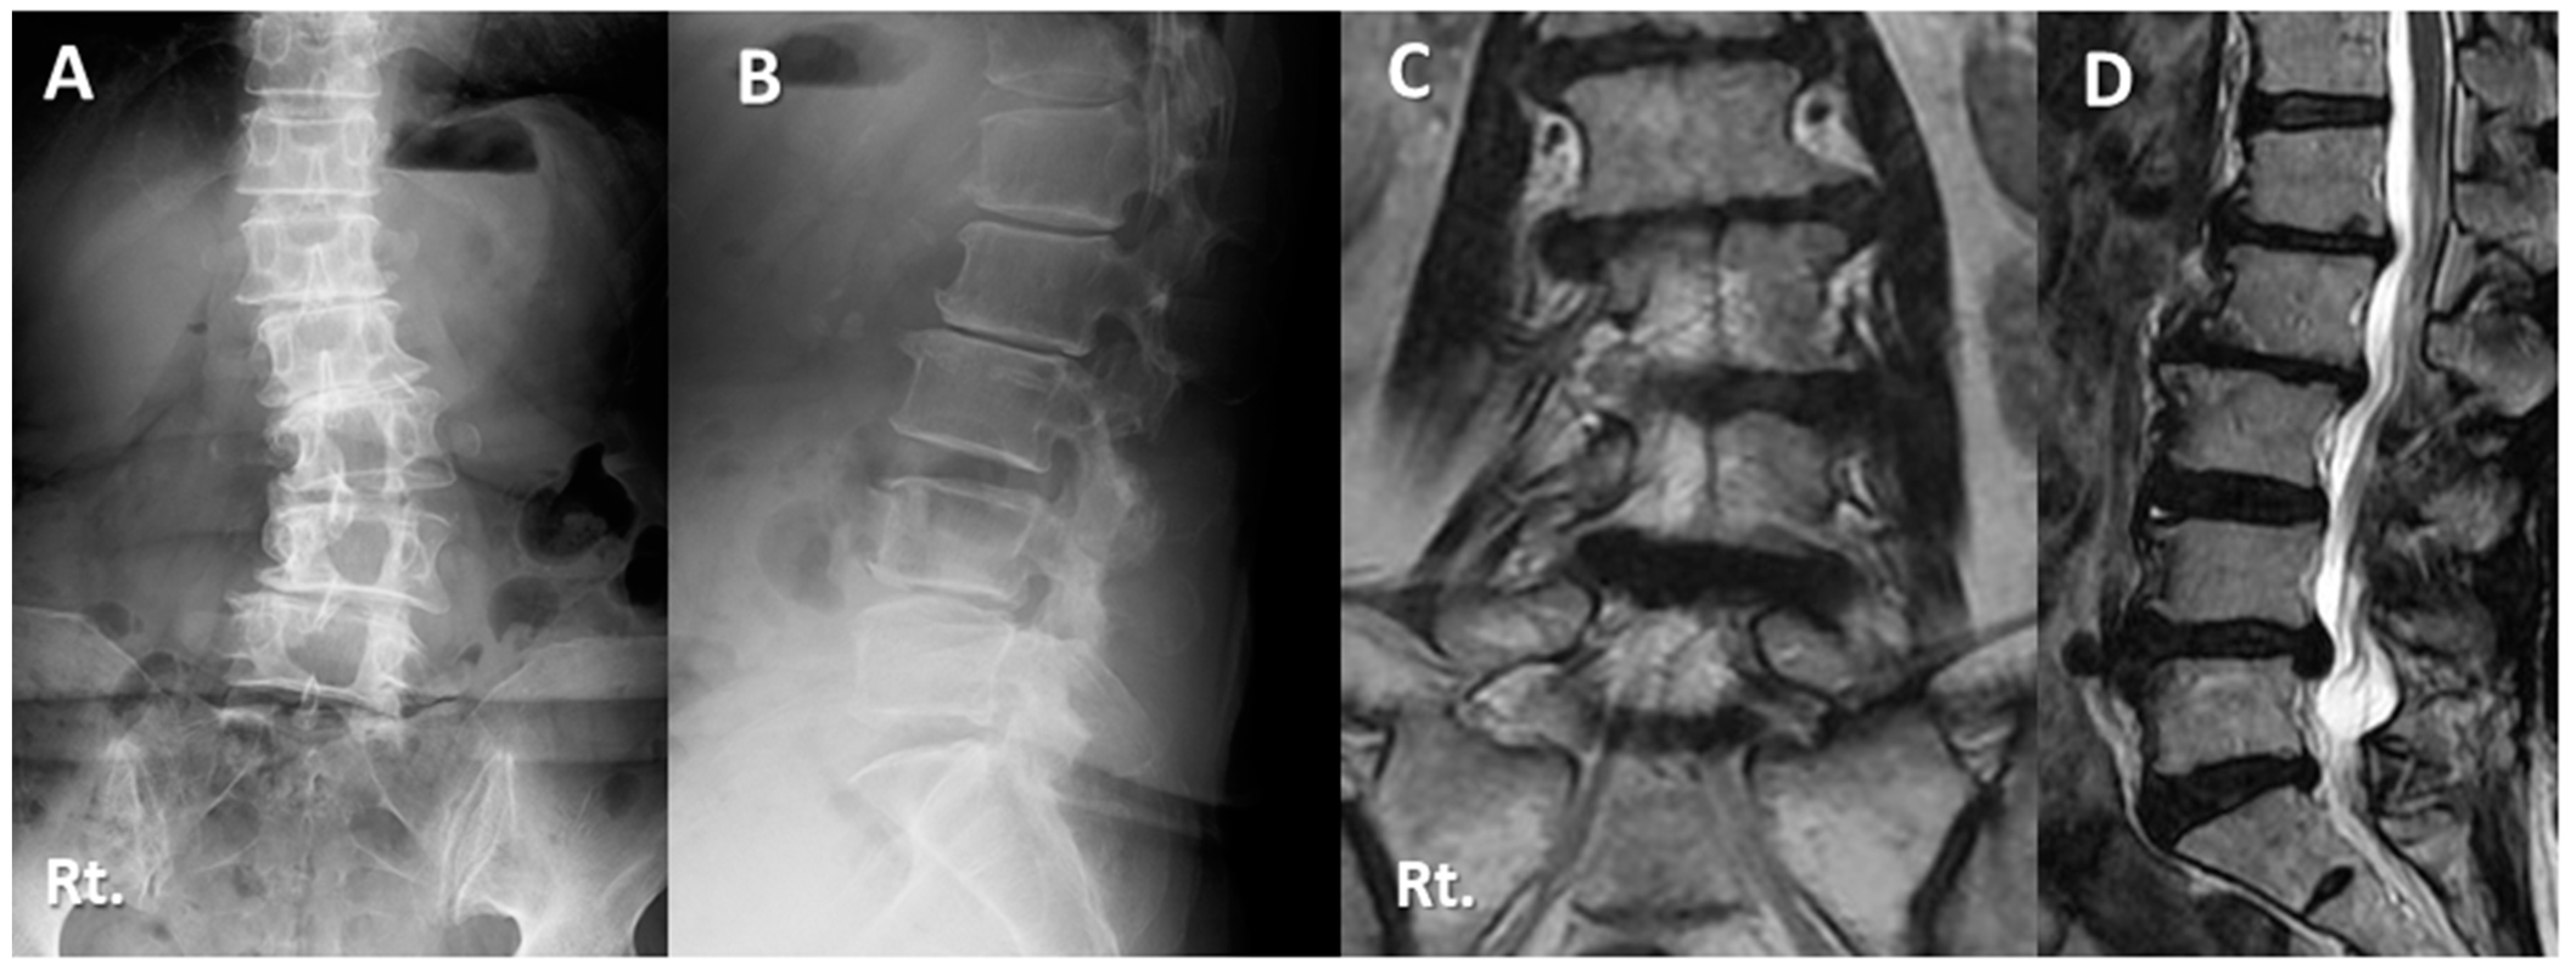

Case Presentations